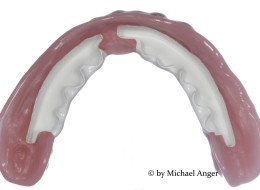

What is PEEK / Was ist PEEK

Aufgrund vielfältiger Nachfragen Due to various requests… Ich versuche, Ihnen hier so viele Informationen wie möglich zu PEEK zusammenzutragen. I’m trying to gather for you as much informations as possible here on the subject of PEEK. Grundsätzlich gibt es viele verschiedene Sorten und Mischungen von PEEK. Basically, there are many different types and mixtures of…